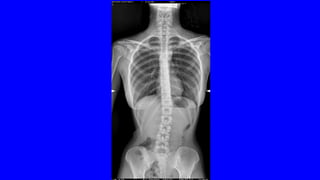

DOLOR CRÓNICO

OSTEOARTICULAR

DOLOR NOCIEPTIVO SOMÁTICO

•ES EL MÁS FRECUENTE

LA ARTROSIS